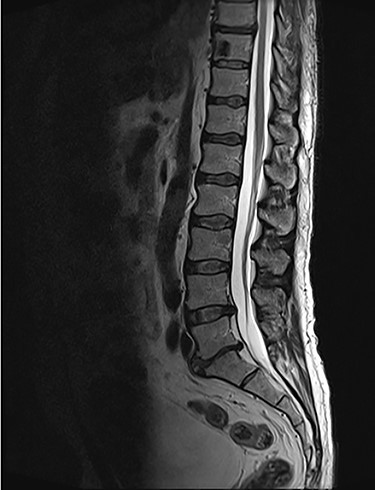

Spinal images are presented in Figs 1–6. Cross-sectional imaging revealed no other neoplastic lesion. He received dexamethasone 10 mg bolus then 4mg four times daily with appropriate proton pump inhibitor coverage. Due to no distinguishable major arterial feeder upon review of the imaging jointly with the neuroradiologist, pre-operative embolization was not attempted. The following morning, he underwent posterolateral right costotransversectomy, ligation of the ipsilateral T4 nerve root, T4 vertebrectomy and insertion of an expandable titanium cage with T1–T7 pedicle screw fixation (Figs 7 and 8). Post-operatively his pain improved to VAS 2/10 and motor power in his left lower limb improved to MRC grade 4/5. The patient was discharged home Day 10 post-admission with physiotherapy.

Sagottal T2W MRI showing synchronous lytic lesions in T10 & L3 vertebral bodies.